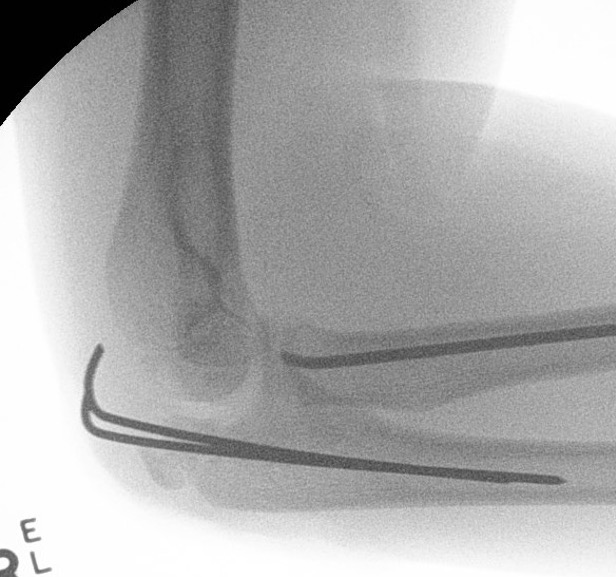

Percutaneous K wire

Technique

Pronate arm to protect PIN

- insert into fracture site

- lever fracture into reduced position

- then drive into opposite cortex